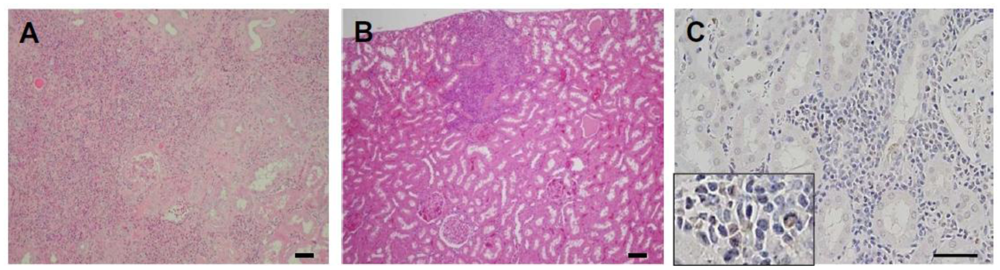

2. Results and Discussion

4. Conclusions